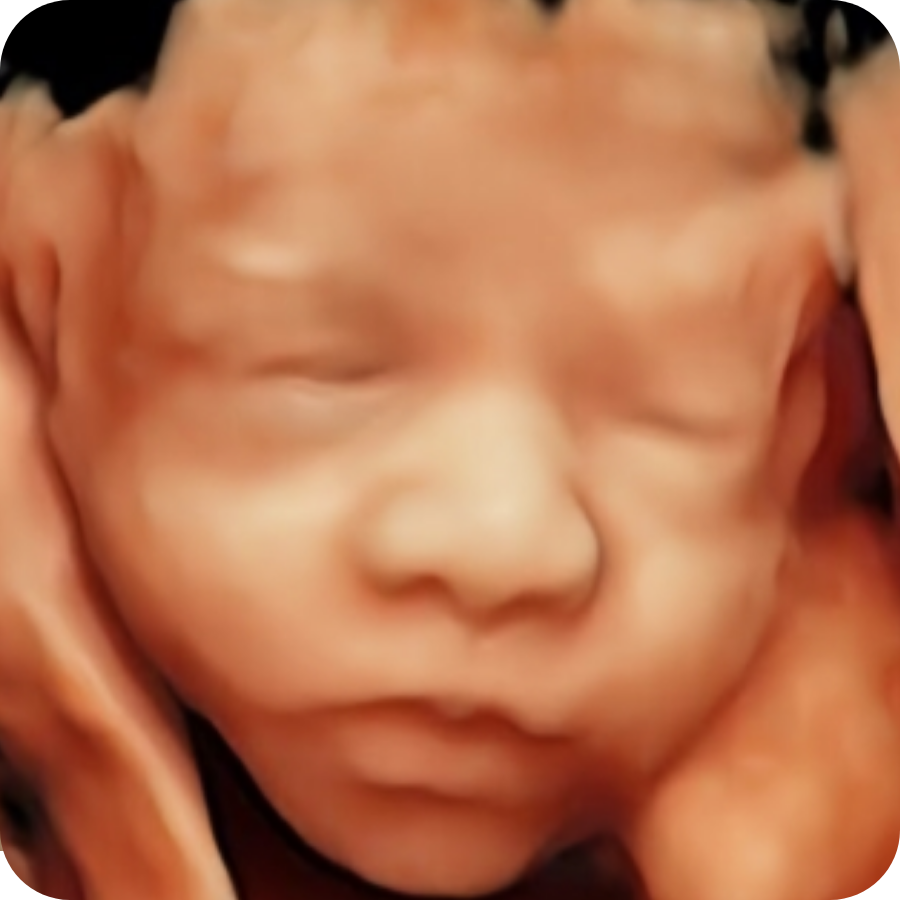

4D & Fetal Wellbeing Scan (£100)

This appointment combines a gestation-appropriate wellbeing review with 4D imaging. The scan is performed by a clinical specialist sonographer and focuses on clear documentation, explanation of findings, and safe signposting if anything needs further assessment.

4D imaging

- We attempt 4D imaging after the clinical portion of the scan.

- Quality depends mainly on fetal position, gestation, maternal tissue, and fluid volume.

- If the face is not well seen, we will be honest about the limitations and focus on the best achievable views.

What you receive (digital-only)

- Same-day report delivered securely via Medifile.

- 2D images from the scan.

- Short video clips where obtainable/recorded.

- For this scan: high-quality 4D images and a short 4D clip where obtainable.